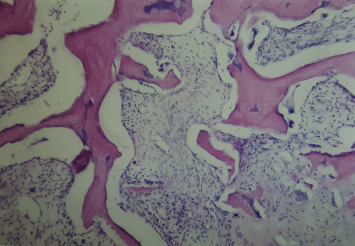

Hematoxylin and Eosin-stained subchondral bone was examined histologically. Hypocellularity and necrosis were seen in all graft bone marrow (Fig. 5 ). However, these factors were more limited in Group 2 than in Groups 1 and 3. Furthermore, in Groups 2 and 3, connective tissue hypertrophy was observed in the bone marrow and subchondral bone. No rabbit developed lymphocyte infiltration in the subchondral bone.

Fig. 5. Hypocellularity and necrosis in bone marrow. Hematoxylin and Eosin staining with original magnification of ×20. |